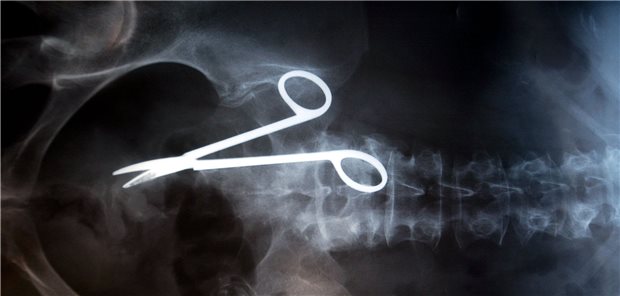

Weniger Patienten als im Vorjahr beschwerten sich 2020 bei der Gutachterkommission für ärztliche Behandlungsfehler in Nordrhein – aus zwei Gründen. Auch der Anteil der festgestellten Fehler sank.